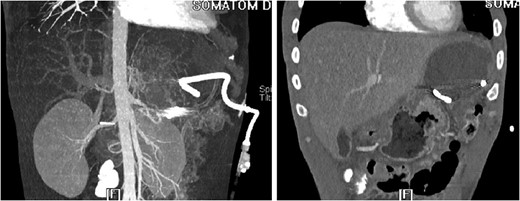

The ‘Islands’ of preserved spleen lit up with IV contrast surrounded by a large collection of old blood and devitalized tissue.

3D reconstruction and coronal CT after placement of pigtail drainage catheter.

Our patient was vaccinated given that post-procedure CT showed the spleen to be partially necrotic with only two islands of well-perfused, preserved spleen depicting >15% decrease in splenic volume. The plan was to perform interval splenectomy however he was lost to follow up.